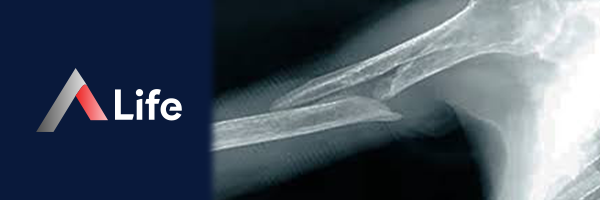

Humerus Kırığı​

Humerus kırığı, kolumuzun üst kısmında bulunan humerus kemiğinin (pazu kemiği) kırılması durumudur. Bu kırıklar, genellikle düşme, spor yaralanmaları veya trafik kazaları gibi travmalar sonucu oluşur.

humerus_k__r__________f23338fd.webp

Humerus Kırığı Türleri

Humerus kırıkları, kırığın yerine göre farklı tiplerde olabilir:

• Proksimal Humerus Kırığı: Omuz eklemine yakın olan humerus başının veya cerrahi boynunun kırılmasıdır. Genellikle yaşlılarda ve osteoporoz (kemik erimesi) hastalarında görülür.

• Humerus Şaft Kırığı: Humerus kemiğinin orta kısmının kırılmasıdır. Genellikle gençlerde ve yüksek enerjili travmalar sonucu görülür.

• Distal Humerus Kırığı: Dirsek eklemine yakın olan humerus kemiğinin kırılmasıdır. Genellikle düşme veya spor yaralanmaları sonucu görülür.

Humerus Kırığı Tedavisi

Humerus kırığı tedavisi, kırığın türüne, yerine ve şiddetine bağlı olarak değişir. Tedavi seçenekleri şunlardır:

• Atel veya Alçı: Kırık kemik uçları yerinden oynamamışsa ve stabilse, atel veya alçı ile tedavi edilebilir.

• Cerrahi: Kırık kemik uçları yerinden oynamışsa veya eklem yüzeyini etkiliyorsa cerrahi müdahale gerekebilir. Cerrahi sırasında, kırık kemik uçları vidalar, plakalar veya çiviler gibi implantlar kullanılarak sabitlenir.

• Fizik Tedavi: Ameliyattan veya alçı tedavisinden sonra, kolun hareketliliğini ve gücünü geri kazanmak için fizik tedavi uygulanır.